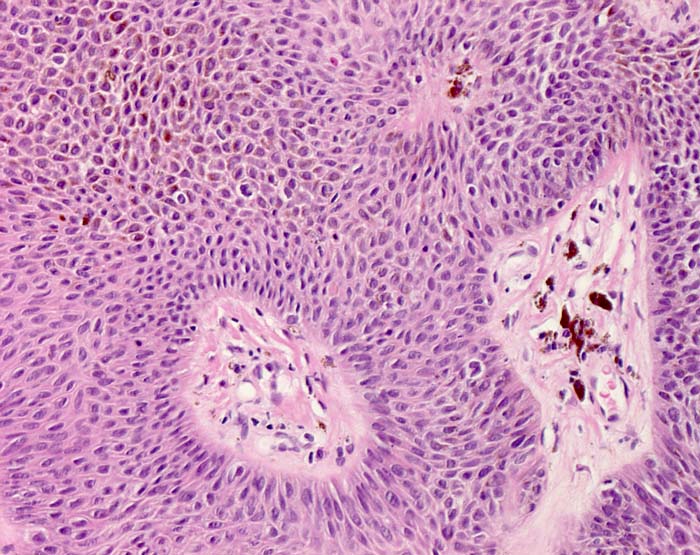

Pigmentierte seborrhoische Keratose vom akanthotischen Typ

Intraepidermale Proliferation monomorpher zytoplasmaarmer basaloider Tumorzellen. Zahlreiche Tumorzellen sind kräftig pigmentiert. Melanophagen in der papillären Dermis.

Hauttumor am Nacken. Melanom?

Histologie

200